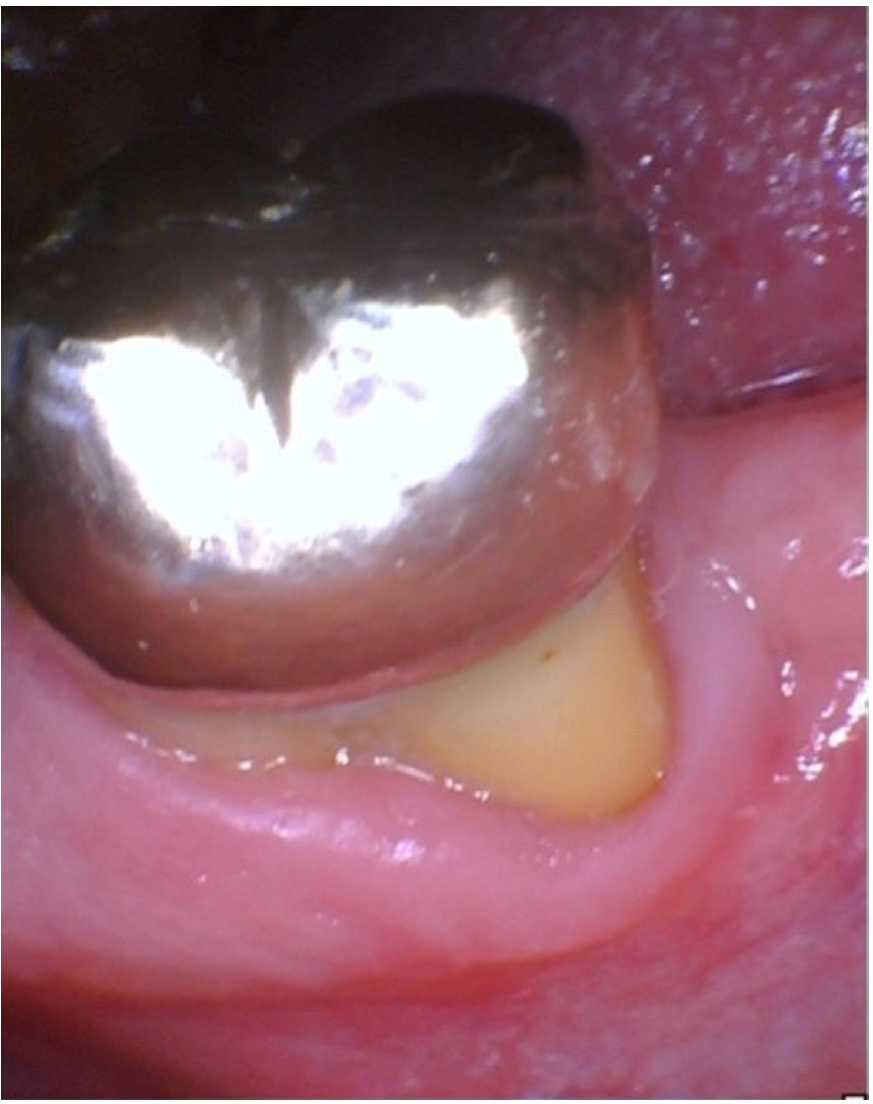

The patient was lost to follow-up until he reported again at 24 months, at which time clinical examination revealed that a full-coverage restoration on tooth #18 had been placed, restoring form and function (Figure 6). Clinical gingival health was noted on a reduced periodontium. Draining sinus tract remained resolved, and probing depths were improved to 3–4 mm. The tooth exhibited no mobility. Periapical radiograph (Figure 7) showed significant resolution of the periapical radiolucency with substantial bone regeneration along the length of the distal root. The patient was greatly appreciative that his natural dentition was conserved, which motivated him to ensure continued dental care maintenance.

Figure 6.

Twenty-four-month recall showing that the tooth has been restored with an extracoronal restoration and absence of draining sinus tract. Gingival health on a reduced periodontium is noted.